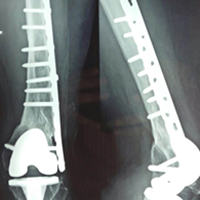

Case:14 Periprosthetic Fracture

60 years old patient with total knee replacement on left knee presented with open grade 1 injury. Debridement & slab given on emergency bases. Fixation with plate & screws done. Union was seen after 6 months.

Pre-Op AP

Pre-Op Lat.

Immdiate Post-op

1 and half months Post-op

2 and half months Post-op

3 and half months Post-op

4 and half months Lateral

6 Years Follow-Up